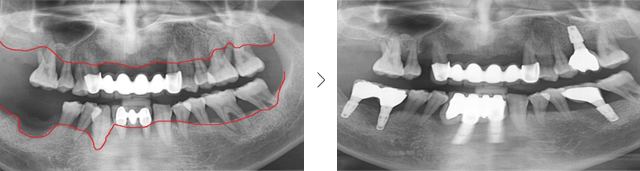

타 치과 에서 6개 치아를 발치하고 12개 임플란트 식립을 진단받고 내원. 고운미소에서 레이저 치주치료로 치아를 보존 시키고 6개의 임플란트 식립한케이스